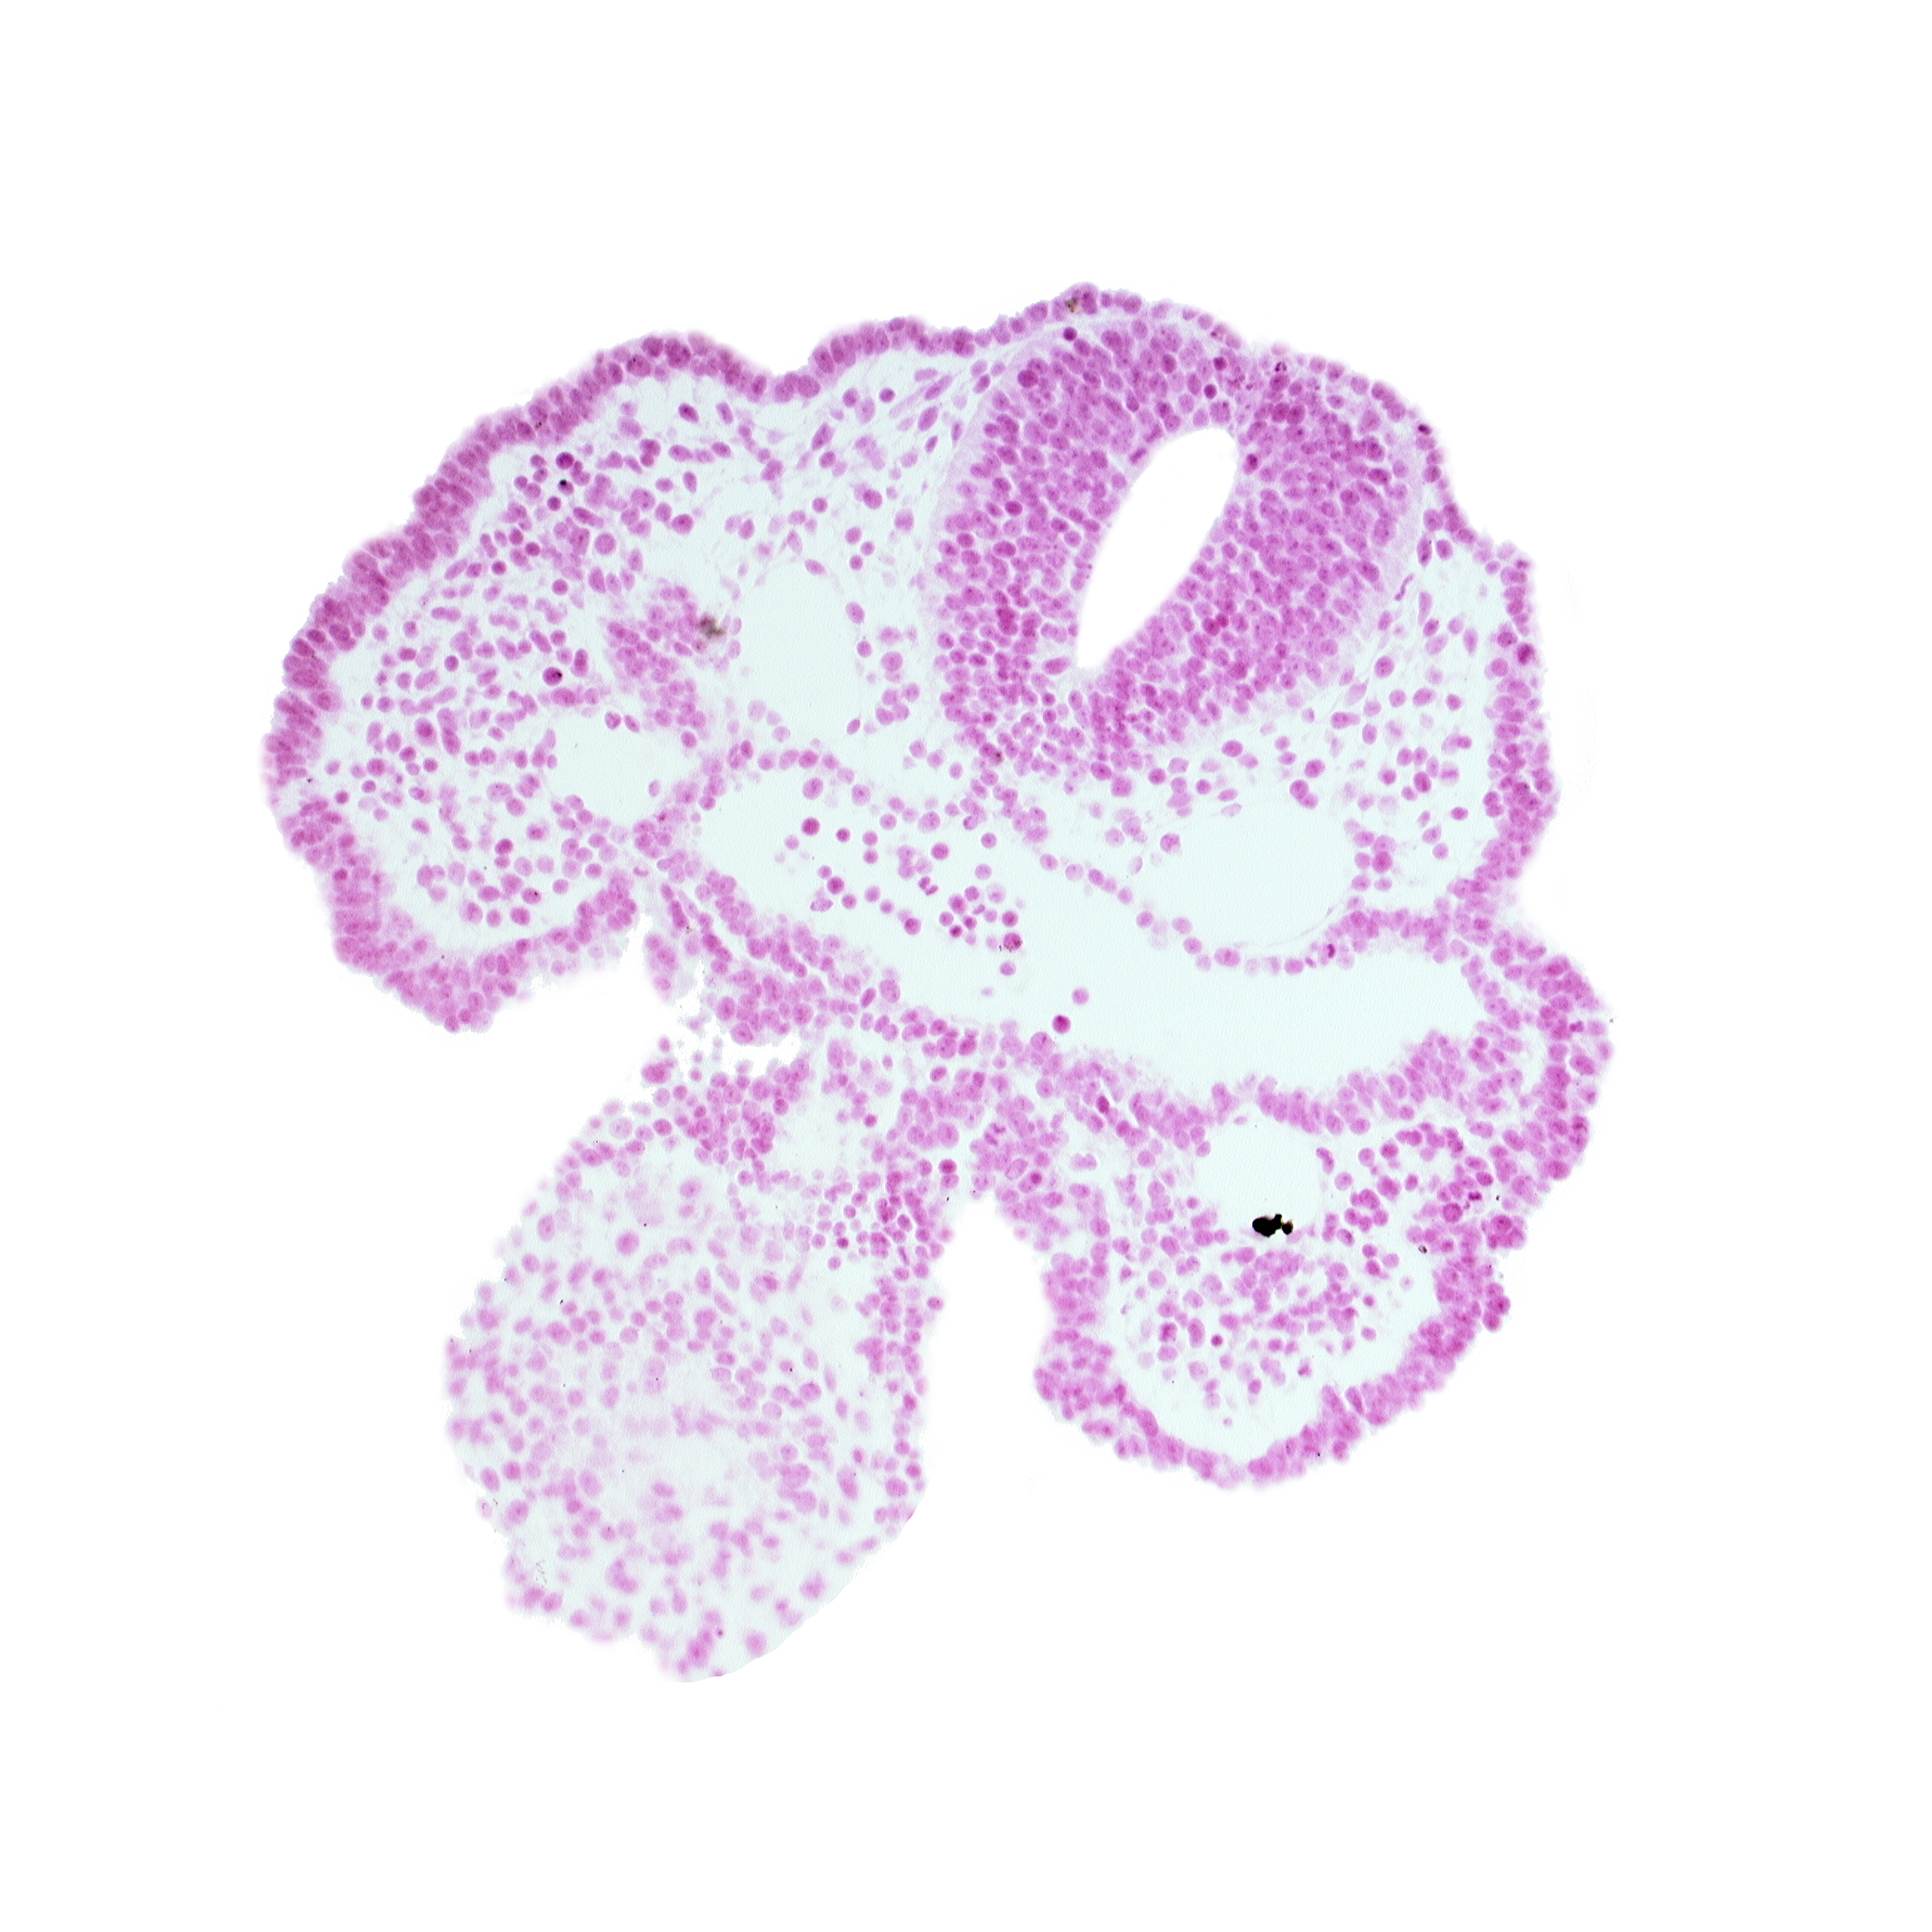

Carnegie Embryo #6344 | Location: 02-08-04

Keywords: caudal part of stomodeum, cephalic part of heart prominence, head mesenchyme, neural tube, notochord, pharyngeal arch 2, pharyngeal groove 1, pharyngeal membrane, pharyngeal pouch 1, surface ectoderm, surface ectoderm (one layer)

Source: The Virtual Human Embryo.